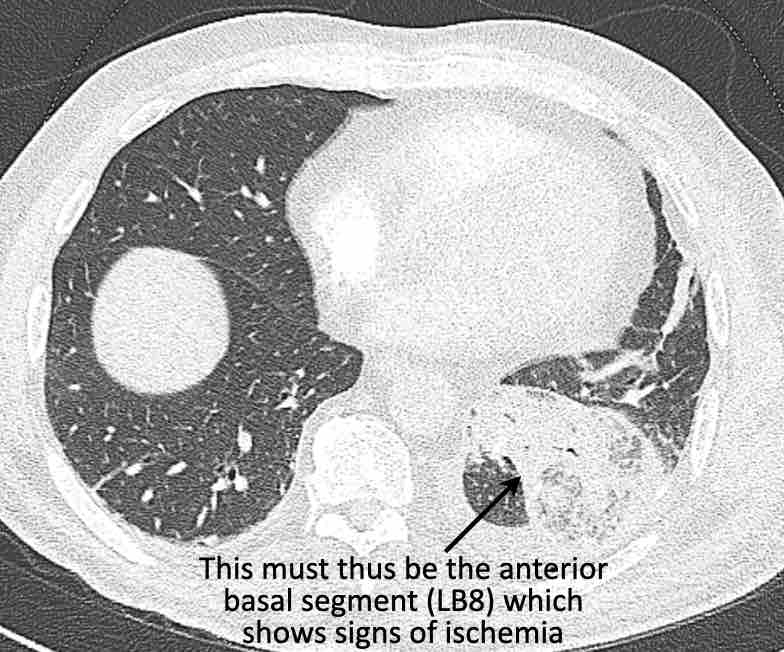

Hình ảnh

Cuộn qua các hình ảnh.

Theo dõi các phế quản của thùy dưới phổi trái cho thấy nhánh phân thùy đầu tiên của thùy dưới phổi trái còn thông; đó là phế quản phân thùy đỉnh.

Các ghim phẫu thuật nằm tại vị trí của các phân thùy đáy sau và đáy bên (LB9/10), vốn thường được cắt bỏ cùng nhau.

Do đó, phân thùy phổi có hình ảnh kính mờ và đông đặc phải là phân thùy đáy trước của thùy dưới phổi trái (LB8).

Động mạch phổi đến phân thùy này cũng không ngấm thuốc cản quang, và bản đồ tưới máu iốt nhấn mạnh thêm tình trạng nhồi máu.

Bệnh nhân đã được phẫu thuật lại và tiến hành cắt bỏ phân thùy bị nhồi máu, với xác nhận qua giải phẫu bệnh.